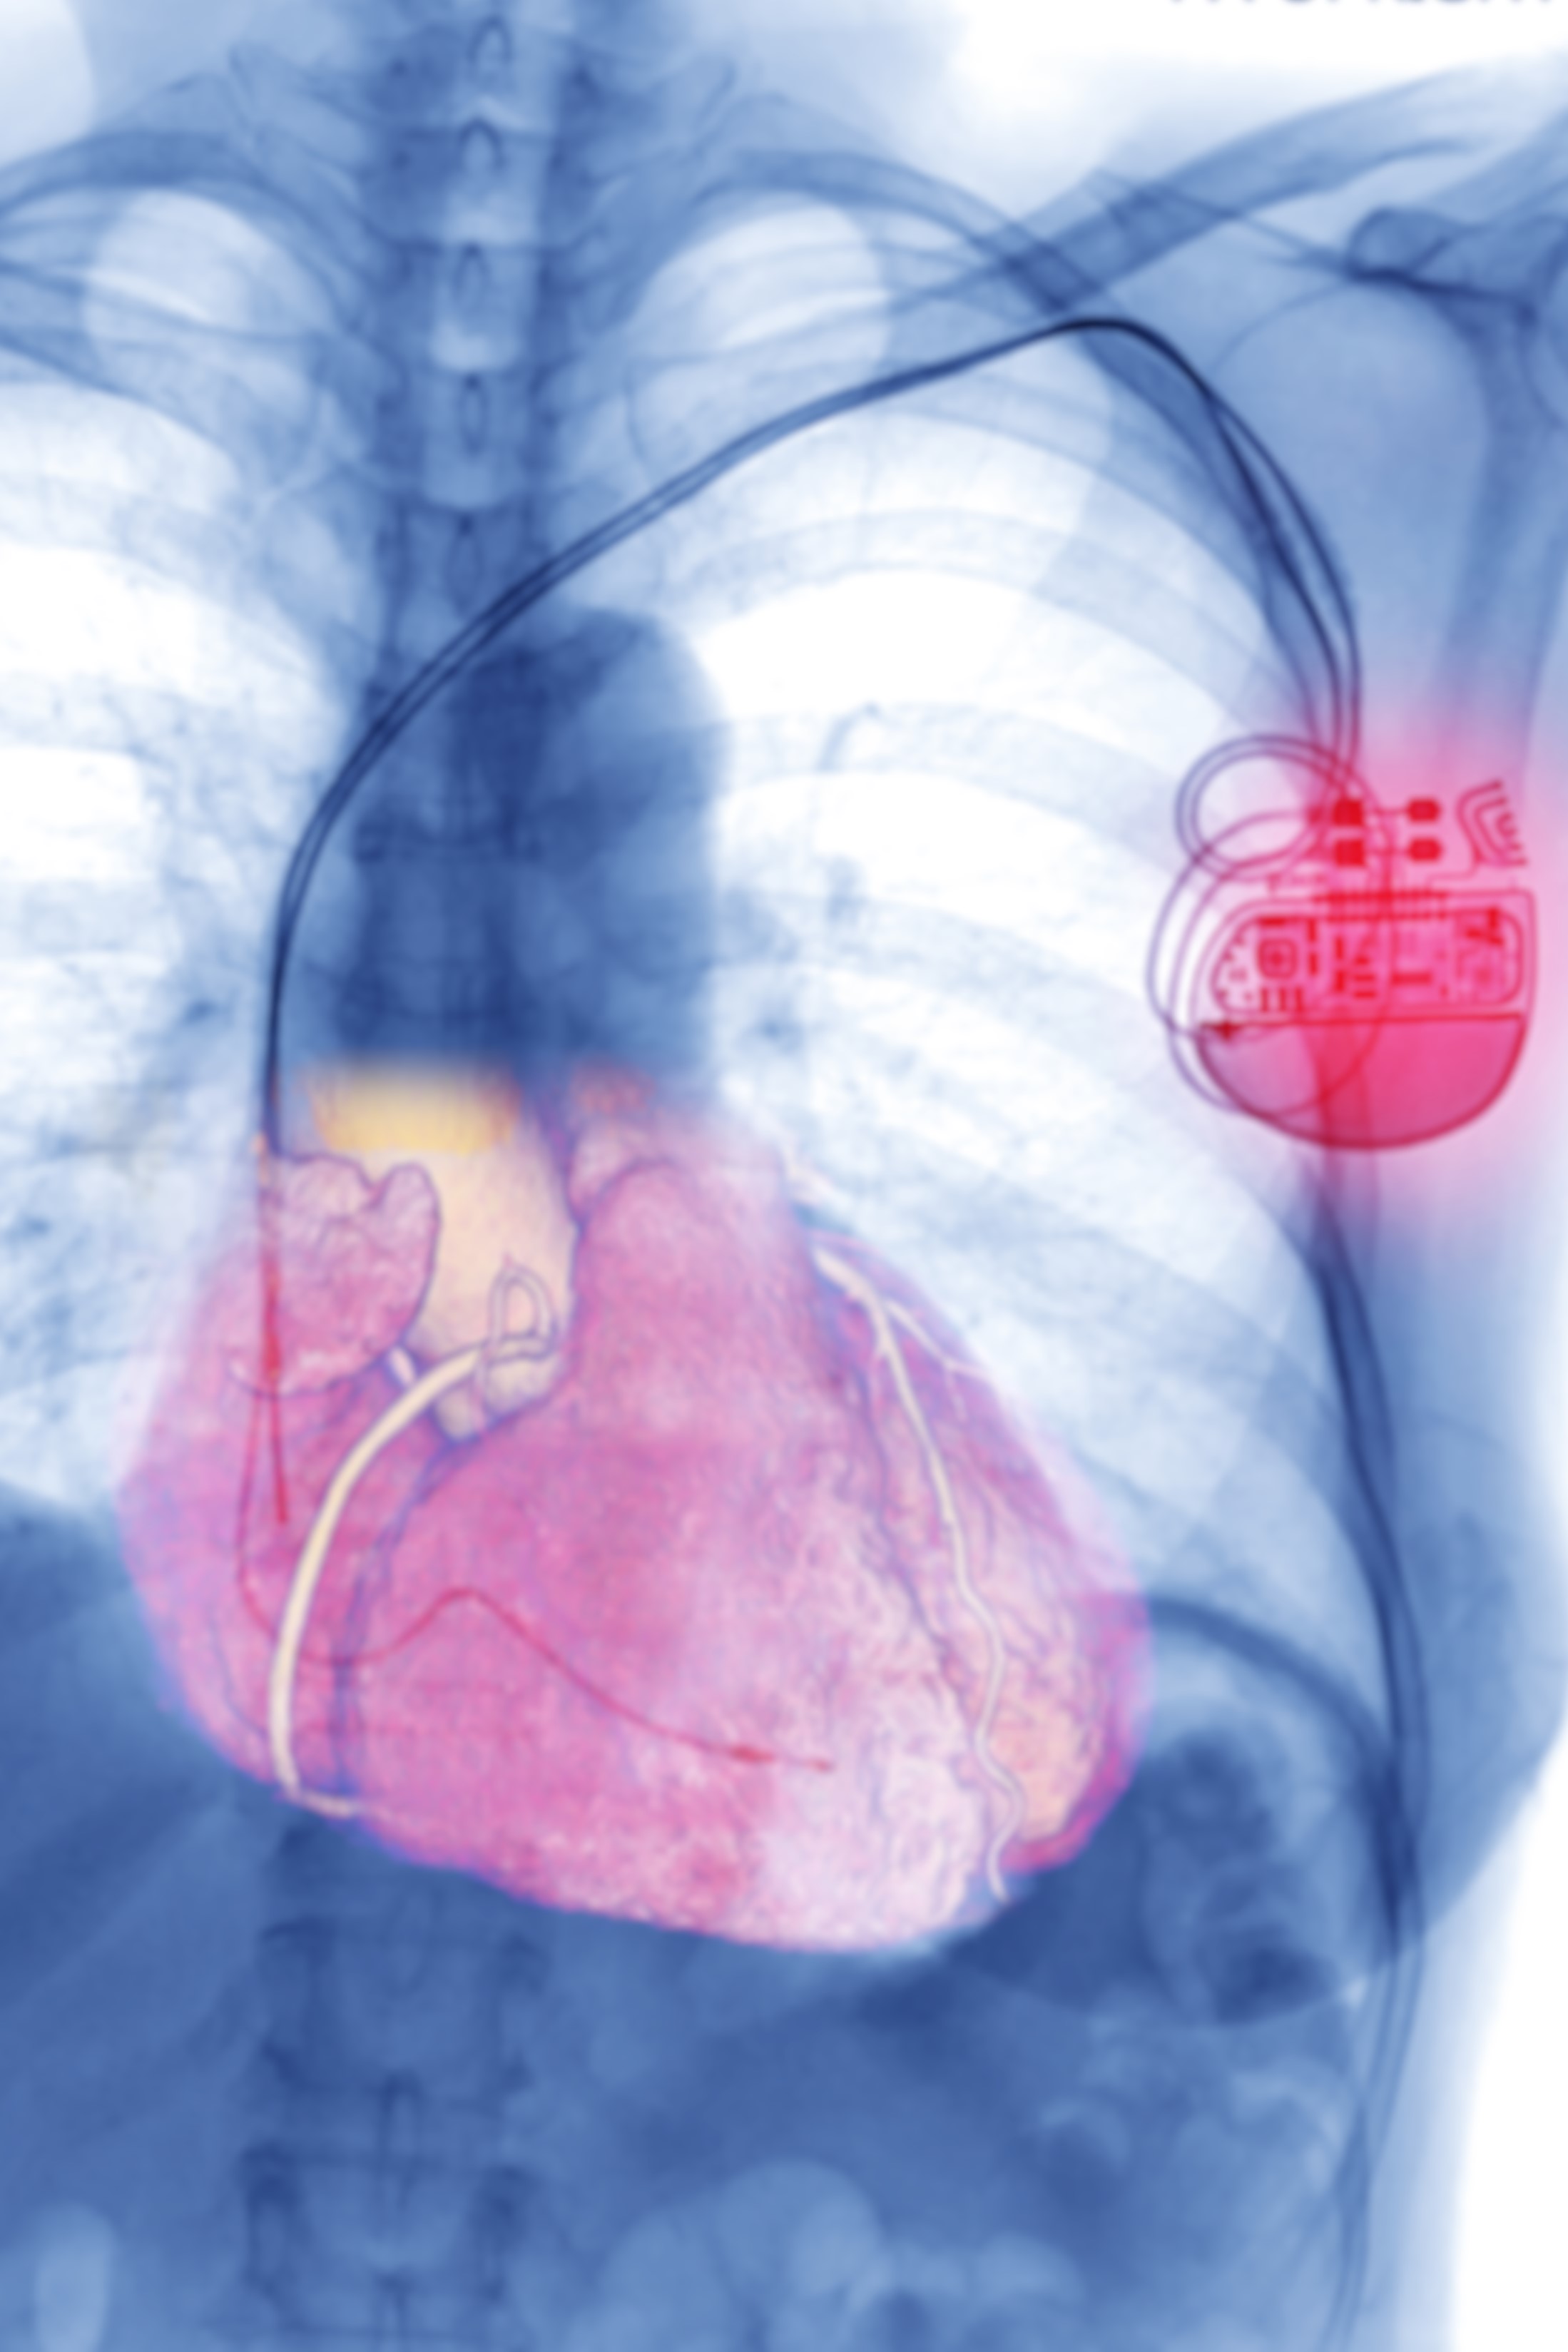

植え込み型除細動器(ICD)

体外式除細動器(AED)を小型化してペースメーカーと同じように体内に植え込む ようにしたものです。薬物療法が奏効しない場合は、発作を感知して自動で電気ショックを 与えるICDの植え込みが検討されます。